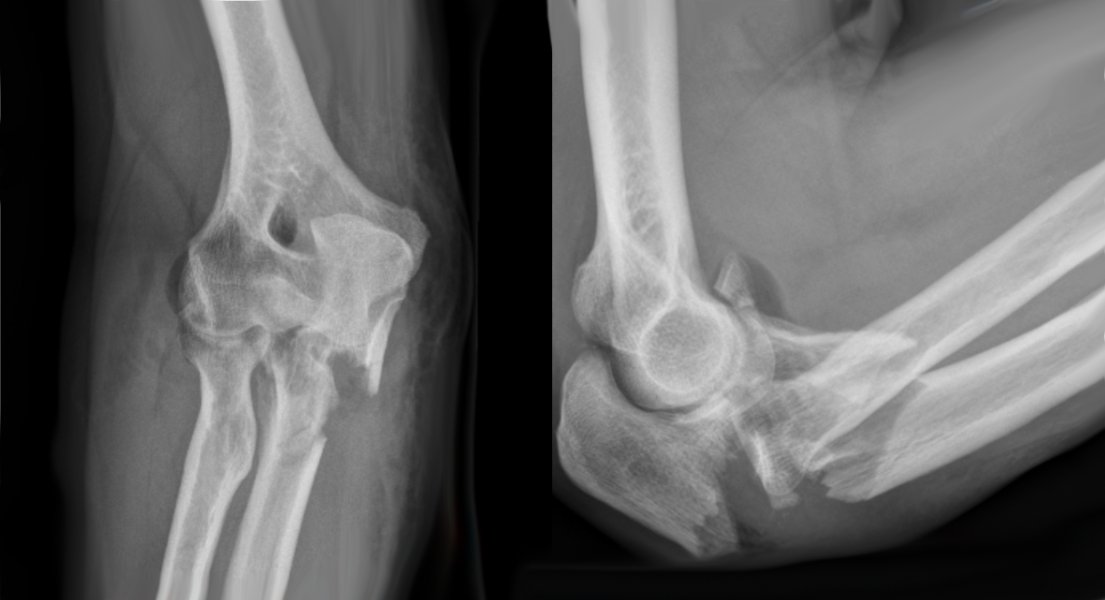

Complex fractures of the elbow may be suspected from the mechanism of injury resulting in pain, deformity and bruising over the elbow. The diagnosis is confirmed on X-rays of the elbow. In some instances a CT scan may be arranged to study the fractures in greater detail and help plan surgical treatment.